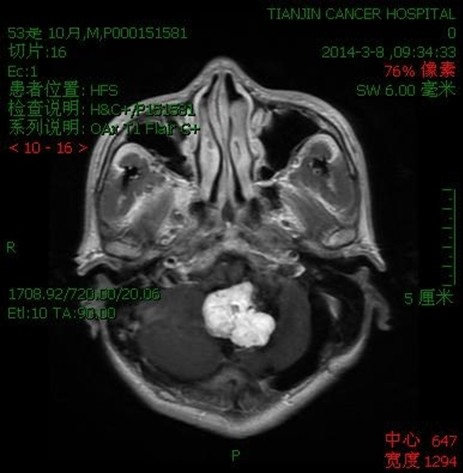

病例二:王**,男性,53岁。因做小脑肿瘤术后9年,头痛头晕,伴颈部疼痛、走路不稳半年入院。入院诊断:延颈交界血管网织细胞瘤。术式:后正中入路延颈交界区血管网织细胞瘤切除术。术后病理:血管网织细胞瘤。术后头痛头晕,颈部疼痛消失,走路平稳。

术前

术后